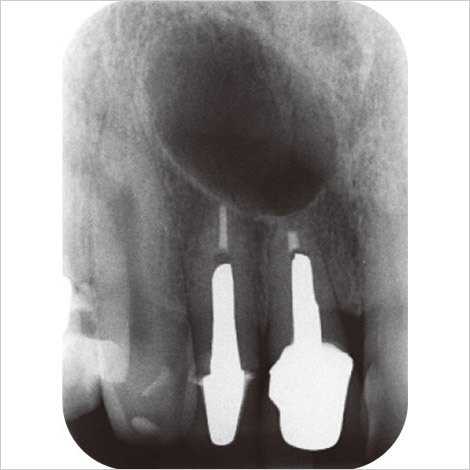

1)根尖病変と根管狭窄(図1)

上顎左側第二大臼歯に痛みを訴えていた。デンタルX線写真(図1)では根尖部に透過像が見られる。根尖透過像の上方に見られる帯状の不透過部は上顎洞底線に頰骨弓が重なったものである。根尖病変と上顎洞の交通はないように見える。本症例で注意しなければならないのは根管が高度に狭窄しているためにほとんど見えないことである。根管だけでなく髄腔も確認できない。慢性の刺激があって第三象牙質が形成され、根管狭搾して歯髄血流が減少し歯髄死に至ったと考えられる。安易に根管治療しようと削り出してはならない。3DX-CT(モリタ)のような高解像度を有する歯科用小照射野CT(CBCT)で歯髄腔狭搾の程度を調べ、対応を検討しなければならない。なお、隣の第一大臼歯は根尖病変こそ見られないものの同じように根管は狭搾している。

図1 66歳女性。上顎左側第二大臼歯の根尖病変。 -